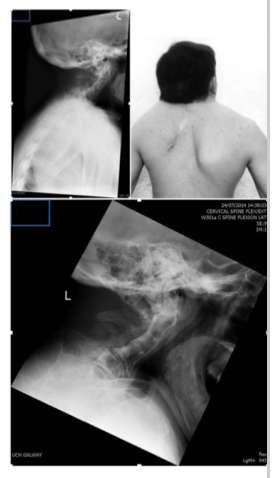

Klippel-Feil Syndrome clinical symptoms

webbed neck

low set hairline - mid thoracic spine

kyphoscoliosis

significant restricted range of movement cervical and thoracic spine